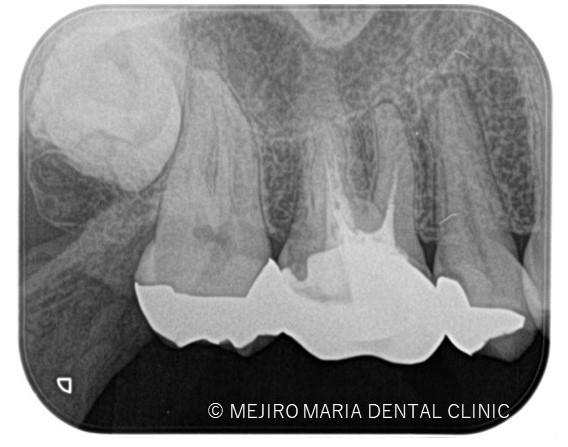

右上の歯牙を4本(右上第一小臼歯〜第二大臼歯)診査したところ、5番には明らかな根尖病変は確認ができません。

しかしながら、歯髄診断を行うと右上5番の歯髄に生活歯髄反応はみられず、歯髄壊死を起因とする根尖性歯周炎の診断に至りました。

診査の結果、右上5番の歯髄には歯髄生活反応は確認できず、歯髄壊死が起因となる根尖性歯周炎と診断しました。術前のレントゲン診査により、根尖が2つに分岐していることを確認できます。